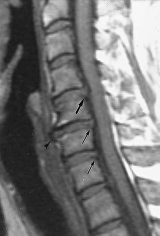

Another situation where confusion can arise is when patients have MRI scans of their spine for symptoms.

Like ‘white matter dots’, there are changes on spinal MRI that happen with age regardless of your age.

By the time you are forty, virtually everyone has a degree of ‘degenerative change’ in their spine. Studies have shown that patients with quite severe changes on their spine often have no symptoms.

But often an MRI report will come back with quite alarming phrases like ‘degenerative changes’, ‘spondylosis’, ‘disc protrusion’, ‘osteophytic lipping’. All of these things imply a spine that is abnormal and damaged, and yet all these things, depending on their severity may be perfectly normal for your age.

Often the most important question is, is there evidence that any nerve roots or the spinal cord have been trapped. Even this can be tricky. Quite often in patients with non-neurological symptoms, like laryngeal problems, MRI has shown alarming looking problems with the spinal cord being squashed, and yet the patient has no symptoms.